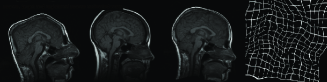

The algorithm is performed both on image scale and on standard intensity scale. Thirty deformed brain images are generated by applying random deformations to the original target images. Original source images are tried to be registered to each deformed target images on standard intensity scale and image scale. Random deformations are obtained by randomly choosing parameters for affine matrix . The resulting deformation field is normalized so that r.m.s displacement is at most 12 pixels. An example for affinely warped images is shown in Figure 6.

In Figure 7, three example registration results of randomly and affinely warped images are shown. The resulting images clearly show that registered source images are in good agreement with target images. Registration quality is measured over 30 randomly deformed images by mean of the square of the differences in intensity (MSE). Experiment has been done both in image scale and on standard scale to show improvement in MSE sense. Table-1 shows the MSE, maximum MSE and minimum MSE over 30 registration examples on image scale and on intensity scale respectively.